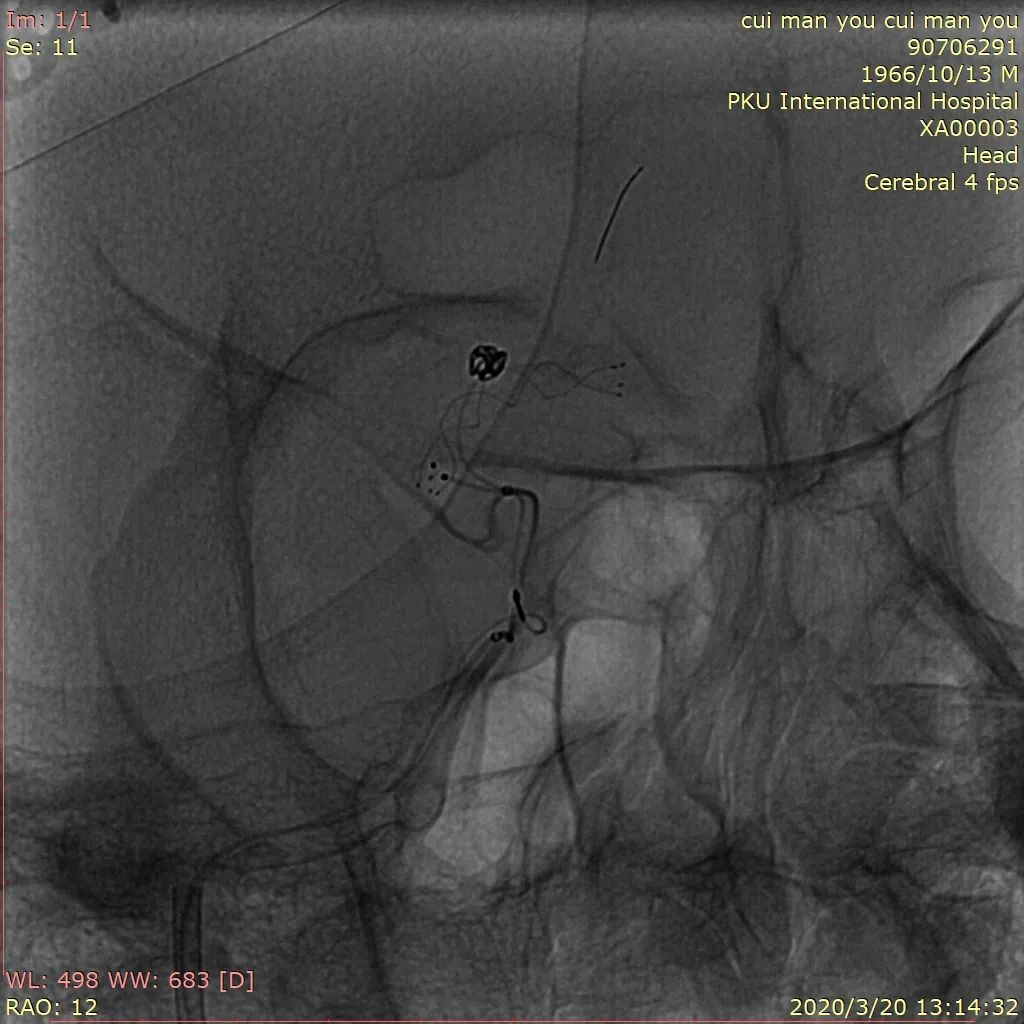

患者取平卧位,全麻满意后,留置尿管通畅,术区常规消毒铺巾,右股动脉行Seldinger穿刺,置入6F动脉鞘,超滑泥鳅导丝携带6FEnvoy行左侧颈内动脉正位造影,压右颈,造影见左侧A1段缺如。将导引导管置于右侧颈内动脉,管头位置满意后造影见右侧A1段动脉瘤,伴子瘤样改变,瘤体近端血管发出。选择合适工作角度,路图指引下,Synchro14微导丝携带Headway21支架管选入右侧A3,撤出微导丝,连接高压肝素水持续滴注。

Synchro14微导丝携带S形塑形后Headwya17微导管反复尝试无法选入动脉瘤内,更换Headway17直头微导管再次尝试,少量回撤支架导管,再次阐释微导管头端进入动脉瘤内。管头位置满意后撤出微导丝,沿微导管送入Target 360 Ultra 2mm×4cm弹簧圈反复调整成篮,暂不解脱,沿支架管送入Lvis3.5mm*15mm支架,于A2打开支架头端缓慢回撤,支架头端位于前交通处时稳定支架管,推送支架,于瘤颈处稍增大力度推送,推送过程见支架尾端向大脑中动脉移行,遂保持张力原位释放,支架尾端部分疝入颈内动脉分叉部,疝出长度约1.5mm。解脱弹簧圈,继续沿微导管送入弹簧圈MicroPlex10 2mm/2cm CosmosComplex,弹簧圈尾端输送时微导管弹出动脉瘤,调整微导管头端位置,解脱后继续沿微导管送入Target 360 Ultra 1.5mm×2cm弹簧圈,输送过程微导管头端无明显移位,弹簧圈位置良好,造影见动脉瘤近全栓塞,载瘤动脉及分支血管通畅,再次尝试送入Target 360 Ultra 1.5mm×2cm弹簧圈,完全推出后调整投射角度,见弹簧圈部分位于支架与血管壁之间,遂撤出弹簧圈,再次造影见动脉瘤近全栓塞,载瘤动脉及分支血管通畅,遂结束手术。撤除各级导管系统,穿刺点封堵止血满意后加压包扎固定良好,患者麻醉苏醒后平车送回病房,术后给予监护、补液、吸氧、右下肢制动24小时、抗血小板等对症治疗,观察患者意识、瞳孔、肢体感觉及运动情况,及时对症处理。

图1 术前造影显示右侧颈内动脉A1段动脉瘤,伴子瘤样改变,返动脉发自瘤体

图4 Headway21及Headway17直头微导管到位,第一枚弹簧圈成篮

图5 Lvis支架释放